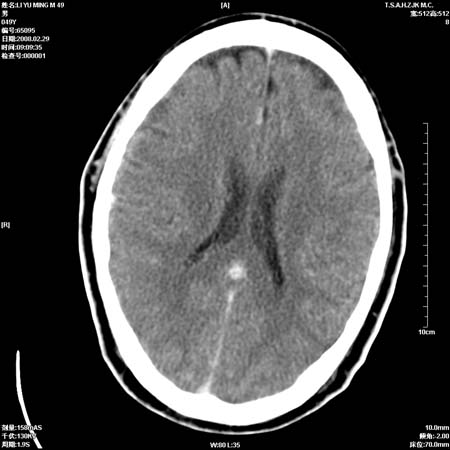

男性, 49岁, 头痛, 行ct检查后, 我科一名大夫报了蛛网膜下腔出血, 请大家讨论!

大脑纵裂池及鞍上池应该有蛛血

支持蛛网膜下腔出血。

一周时间密度未见改变,考虑为正常图像(脑动脉硬化?)。